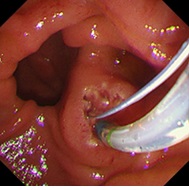

乳頭切開

バルーンによるに乳頭拡張